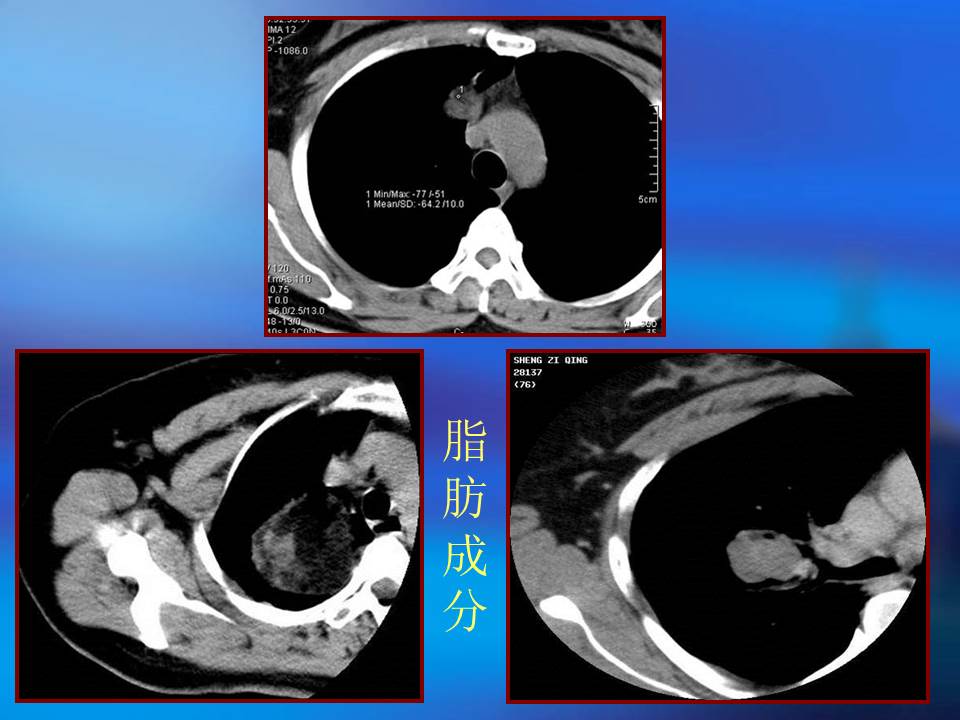

幻灯片3